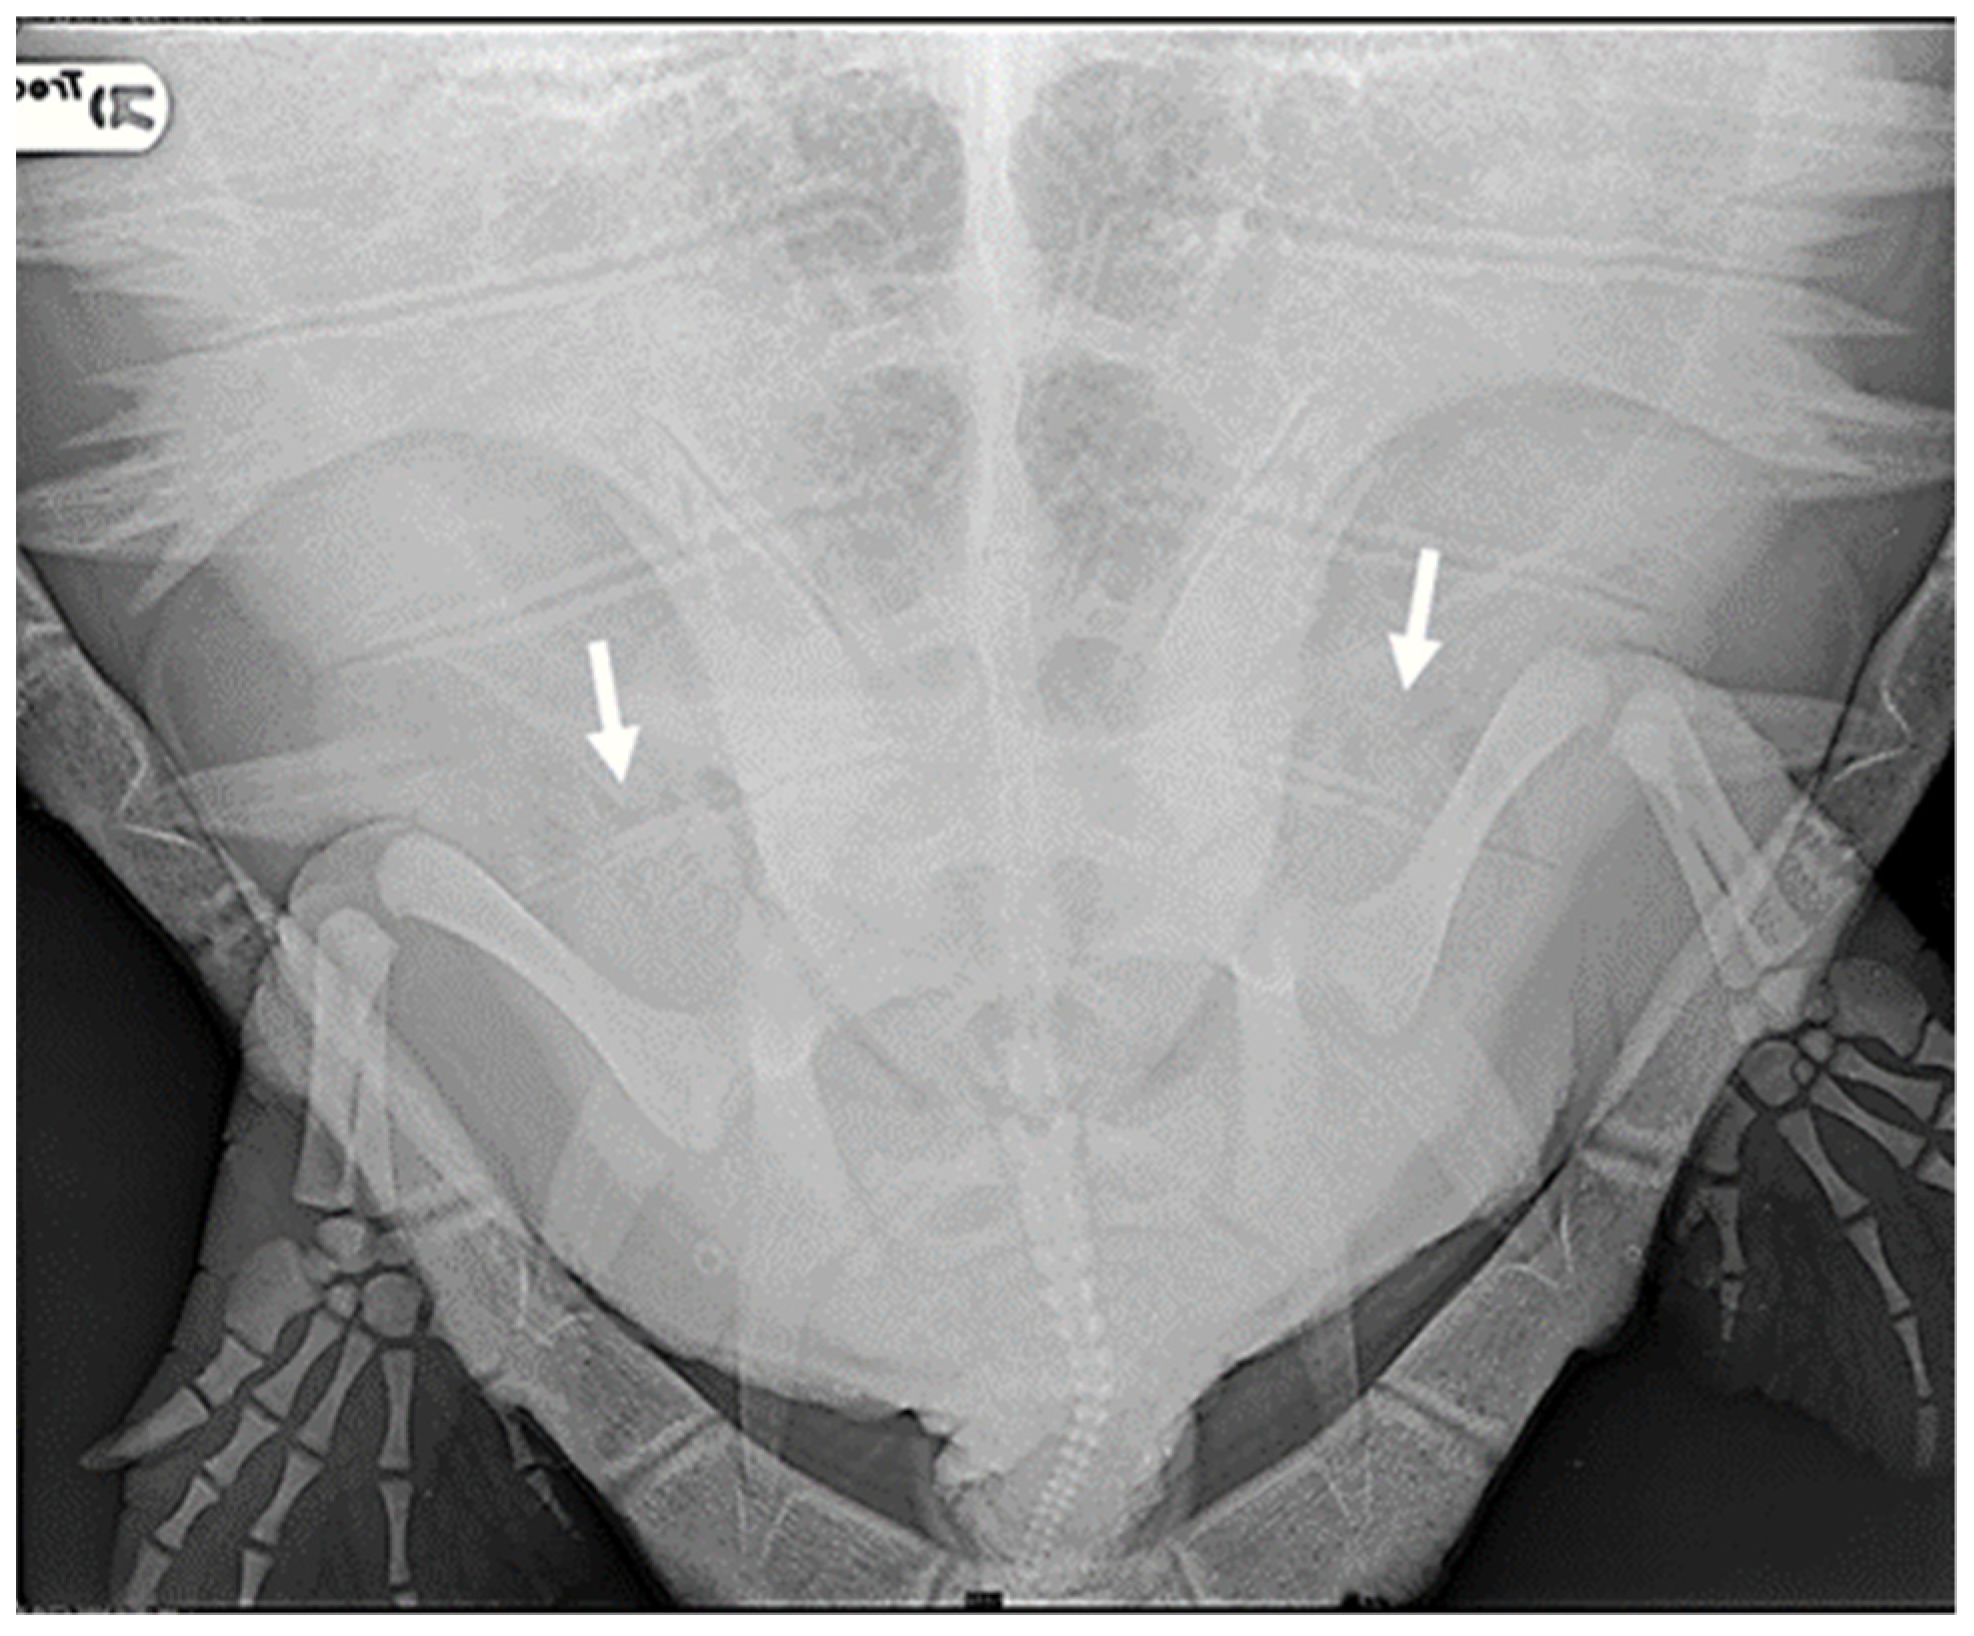

Four subjects were classified as having moderate severity of GE (13.8%): in addition to the renal and marginal-costal vessels, a notable distribution of gas was identified in several other vascular districts, including hepatic vessels, inferior mesenteric artery, gastric artery, abdominal transverse vein, iliac arteries, and veins (Figure 2).

Six turtles were categorized as severe (20.7%) because, apart from all the more peripheral districts, a significant presence of gas was observed in central vascular districts such as the precava vein, postcava vein, venous sinus, left atrium, pulmonary artery and vein, pulmonary trunk, aorta, and brachiocephalic trunk (Figure 3).

Figure 2. X-ray examination in DV projection of a subject diagnosed with moderate severity GE reveals the presence of gas in various vessels, including the gastric vessels (white arrow), inferior mesenteric artery (white empty arrow), iliac vessels (black arrow), and duodenal vein (black empty arrow). The present gas overlaps the lungs’ cranial area, reducing the visualization of lung volume.

Figure 3. X-ray examination in DV projection of a subject diagnosed with severe GE. An evident massive presence of gas in the majority of vessels: (a) the white arrow shows the subclavian artery; (b) the white arrow shows the massive presence in the precaval vein, the white empty arrow the postcava vein, the black arrow the transverse vein, obscuring a full view of the lung areas.